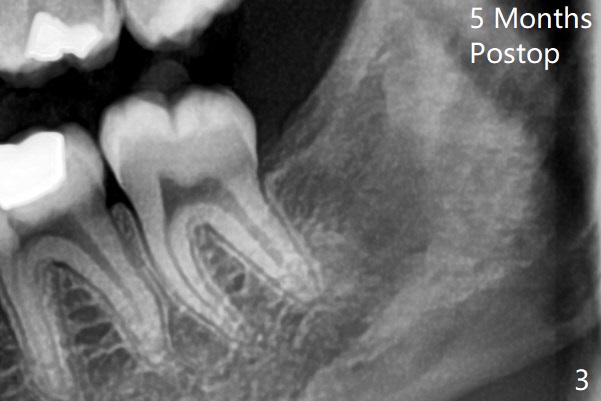

截骨后牙齿容易松动,然后切断两次,顺利拔除,放置Osteogen Plug,4-0 铬羊肠线缝合(图二);近中牙槽嵴中断。5个月后左下智齿牙槽窝愈合(图三);近中牙槽嵴重建。